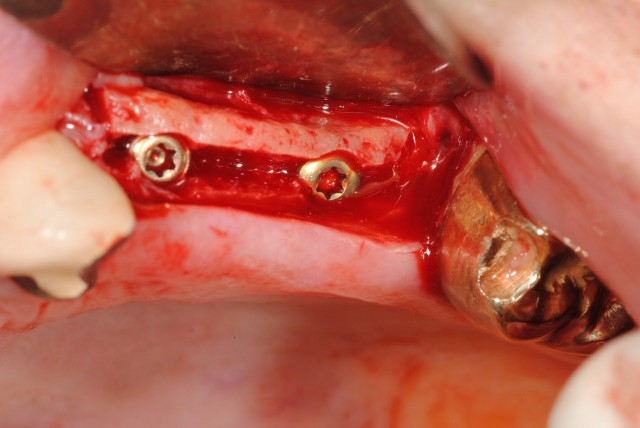

This article discusses multiple methods of uncovering an implant during second stage surgery for ideal tissue esthetics.